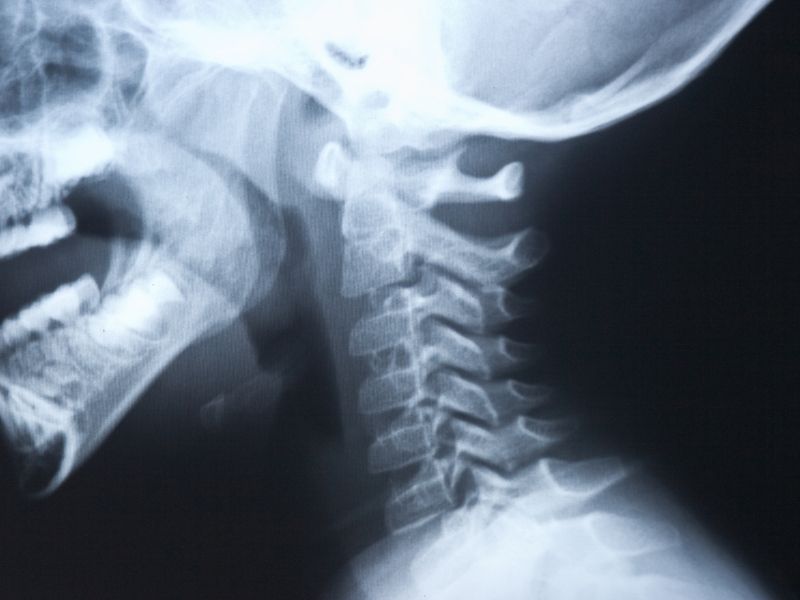

Doktorunuz muayene esnasında yaralanmanın şekli, ağrının karekteri ile ilgili sorular soracaktır, bununla beraber gerginliğin olduğu bölgeleri eli ile muayene edecektir. Kemik yapıları gözlemlemek için röntgenler istenebilir. Röntgenlerde kırık, artrit, gibi ağrıya etken olabilecek sebebler aranacaktır. Zaman zaman ayırıcı tanıda MR gibi ileri tetkik yöntemleri kullanılabilir.